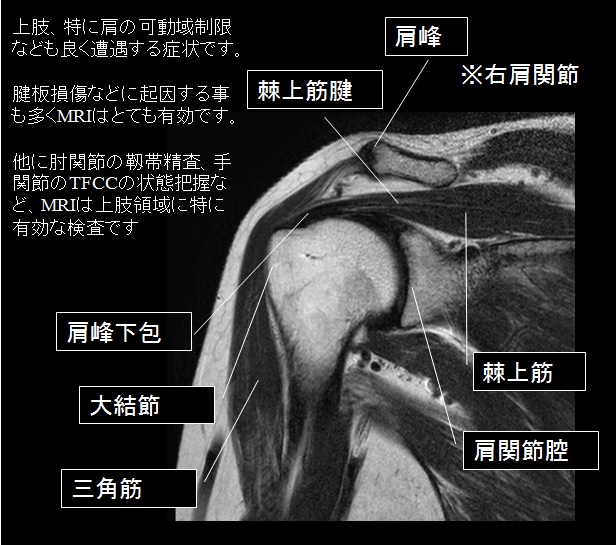

肩関節のMRI−読影ポイントと新しい知見−第3版 | 佐志 隆士

肩関節のMRI−読影ポイントと新しい知見−第3版 | 佐志 隆士